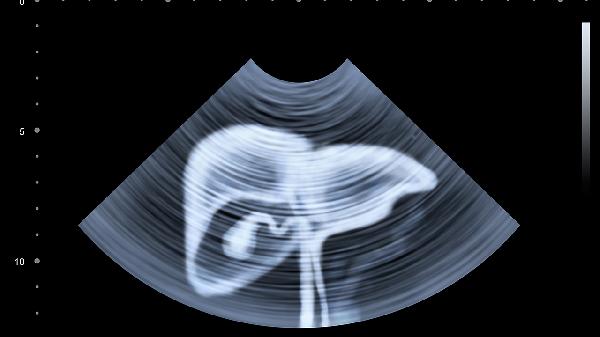

右腹部肋骨下隐隐作痛怎么办

右腹部肋骨下隐隐作痛可通过调整饮食、热敷、药物治疗、中医调理、手术治疗等方式缓解。右腹部肋骨下隐隐作痛可能与胆囊炎、肝炎、肋软骨炎、胃肠功能紊乱、外伤等因素有关。

右腹部肋骨下隐隐作痛可能与胆囊炎有关,通常表现为右上腹疼痛、恶心等症状。可遵医嘱使用消炎利胆片、胆舒胶囊、熊去氧胆酸胶囊等药物进行治疗。消炎利胆片具有清热祛湿、消炎利胆的功效,胆舒胶囊可疏肝理气、利胆溶石,熊去氧胆酸胶囊能促进胆汁分泌。

右腹部肋骨下隐隐作痛可能与胆囊结石有关,通常表现为阵发性绞痛、黄疸等症状。若结石较大或反复发作,可考虑行腹腔镜胆囊切除术或开腹胆囊切除术。术后需注意伤口护理,避免剧烈运动,遵医嘱定期复查。